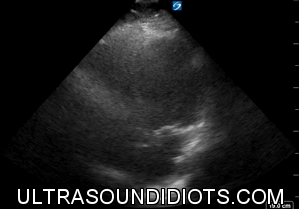

LAD Lesions

CORONARY ANATOMY REMINDER